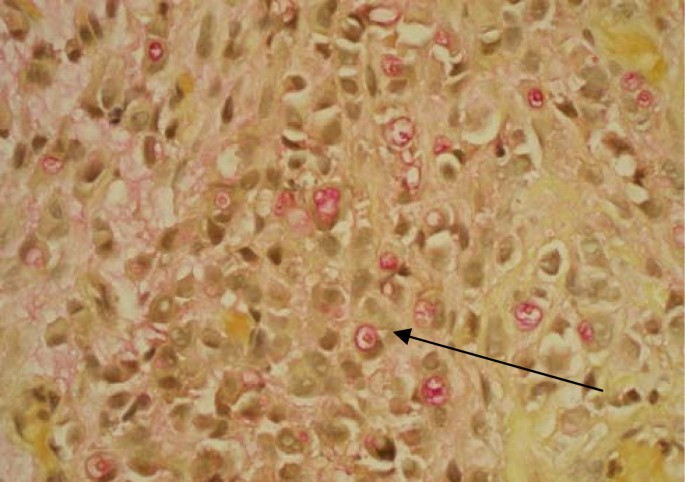

A 58 year old previously healthy Caucasian male presented with a five month history of increased frequency of urination, feeling of incomplete emptying and nocturia. He denied any history of fever, hematuria, nausea, vomiting or diarrhea. He complained of approximate 10 pound weight loss over a period of 1 week. He reported a previous diagnosis of enlarged prostate with a normal Prostate Specific Antigen (PSA). He also reported a recent history of "small heart attack" for which he was medically treated at an outlying facility where he was also informed about poor kidney function. He also gave history of recently diagnosed hypertension and a 80 pack year of ongoing smoking. His medications included amlodipine, finasteride, doxazosin, metoprolol, clopidrogel, aspirin and lovastatin. All of these were started 5 days prior to presentation. Physical examination revealed a healthy appearing male with normal vital signs. His rectal exam revealed a slightly enlarged, non-tender prostate. Rest of the physical exam was unremarkable. Laboratory data revealed hemoglobin 10.3 g/dl, blood urea nitrogen 24 mg/dl, creatinine 2.7 mg/dl, and PSA level 0.18 ng/ml. Urinalysis was negative for RBC's, WBC's, bacteria, or nitrates. Retroperitoneal ultrasound showed normal sized kidneys with mild pyelocaliectasis bilaterally, prostate measured 4 × 2.7 × 2.6 cm with homogenous echotexture, otherwise unremarkable. Immediately after placement of foley catheter he had 650 ml of urine output. Blood urea nitrogen decreased to 18 mg/dl and serum creatinine decreased to 1.7 mg/dl. His azotemia was thought to be secondary to BPH and he was discharged with indwelling foley catheter to be followed up as an outpatient. At outpatient clinic, on removal of his foley catheter, his post void residual was found to be 150 ml. Various management options including surgical interventions were discussed with the patient in detail. After discussion patient was discharged home to be followed up as an outpatient but was started on tamsulosin. He returned to the hospital with complaints of urgency and frequency. His creatinine had increased to 5.0 mg/dl. Abdominal CT at this time revealed bilateral hydronephrosis and hydroureter (Figure 1 and 2). This finding was confirmed on retrograde pyelogram. Cystography showed marked thickening of the urinary bladder trabeculae (Figure 3). Cystoscopy revealed the entire bladder mucosa to be thickened and edematous with an exaggerated granular type appearance and bilateral uretero-vesical junction stenosis prompting placement of bilateral ureteral stents. He subsequently had a diuresis producing 6 liters of urine. This was followed by a reduction in the serum creatinine from 5.2 to 3.1 mg/dl over two days. Pathological analysis of tissue from random bladder wall biopsies at the time of cystoscopy revealed an infiltrate of cells beneath the surface epithelium (Figure 4). These cells were described as small, with a high nuclear-cytoplasmic ratio. Many cells showed a cytoplasmic vacuolization with displacement of crescentic, hyperchromatic nuclei (Figure 5). Special stain results were positive for mucin (Figure 6), pan-cytokeratin, CK7 and CK20 but negative for PSA and PAP (prostatic acid phosphatase). Based on these results, a diagnosis of Primary Signet Ring Cell Carcinoma (PSRCC) of the bladder was established. He underwent esophagogastroduodenoscopy and colonoscopy to evaluate possible primary site of his malignancy but were found to be negative. Management plans were then made for radical cystectomy. But the subsequent course was complicated by colitis secondary to Clostridium difficile requiring total colectomy with diverting ileostomy. Pathologic evaluation of the removed colon showed no evidence of malignant involvement. Recovery was further complicated by myocardial infarction requiring coronary artery bypass grafting. The patient failed to recover and continued to deteriorate. After discussion with family his care was transferred to hospice and he passed away. Cystectomy was therefore not performed.

Signet ring cells are described as crescent shaped cells containing nuclei compressed to one edge of the cell by large amounts of cytoplasmic mucin appearing as a single clear vacuole in some tumors and as a foamy, multivesicular cytoplasmic material in others [4, 8]. Mucin accumulations form in the cytoplasm and nuclei are unevenly distributed [7]. Routine mucin staining of otherwise normal transitional cell carcinoma will reveal signet ring cells in many cases and the exact percentage of signet ring cells that must be present in order to make the diagnosis of PSRCC of the bladder has not been established. Holmang and associates suggested that 50-60% of the tumor should be made up of signet-ring cells to make this classification [2]. However, because the linitis plastica-like pattern of diffuse signet-ring cell infiltration is associated with a poorer prognosis, it has been suggested that only this pattern should be considered a pure signet-ring cell carcinoma [4]. Bladder tumors found to consist solely of signet-ring cells should prompt a thorough search for a distant primary site. Those consisting of a mix of signet-ring cells and transitional cells are more likely to be of primary bladder origin [1]. Also, PSRCC is usually a solitary lesion (63%) in contrast to transitional cell carcinoma which is most often multifocal (66%) [8].